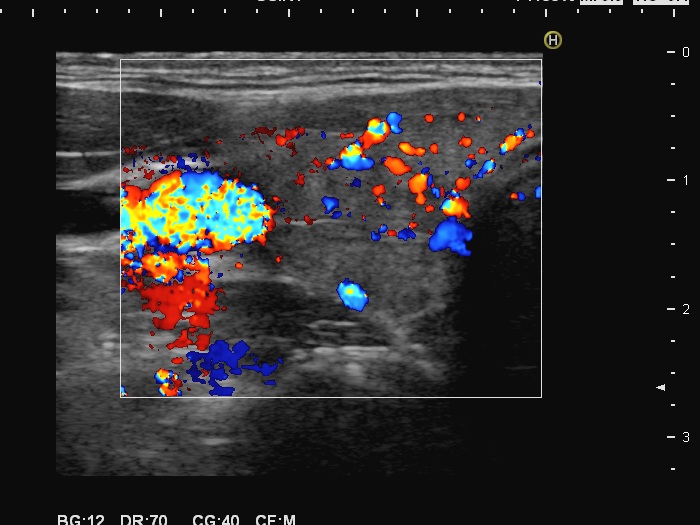

Left lobe, color Doppler mode

This is the usual course of Graves' disease regarding the change in echo pattern - before, during and after the activity of the autoimmune process. The only exception is the change in the size of the thyroid. In most cases, the thyroid increases during the activity of the disease, then returns to normal. However, in this patient the age counts: at the first examination, the patient was only 15-year-old.

- There are two situations in Graves 'disease where circulation is increased. At the stage of disease activity and when hypothyroidism is observed with medication. In the former case, the blood flow is almost always increased, in the latter it can be decreased and increased.